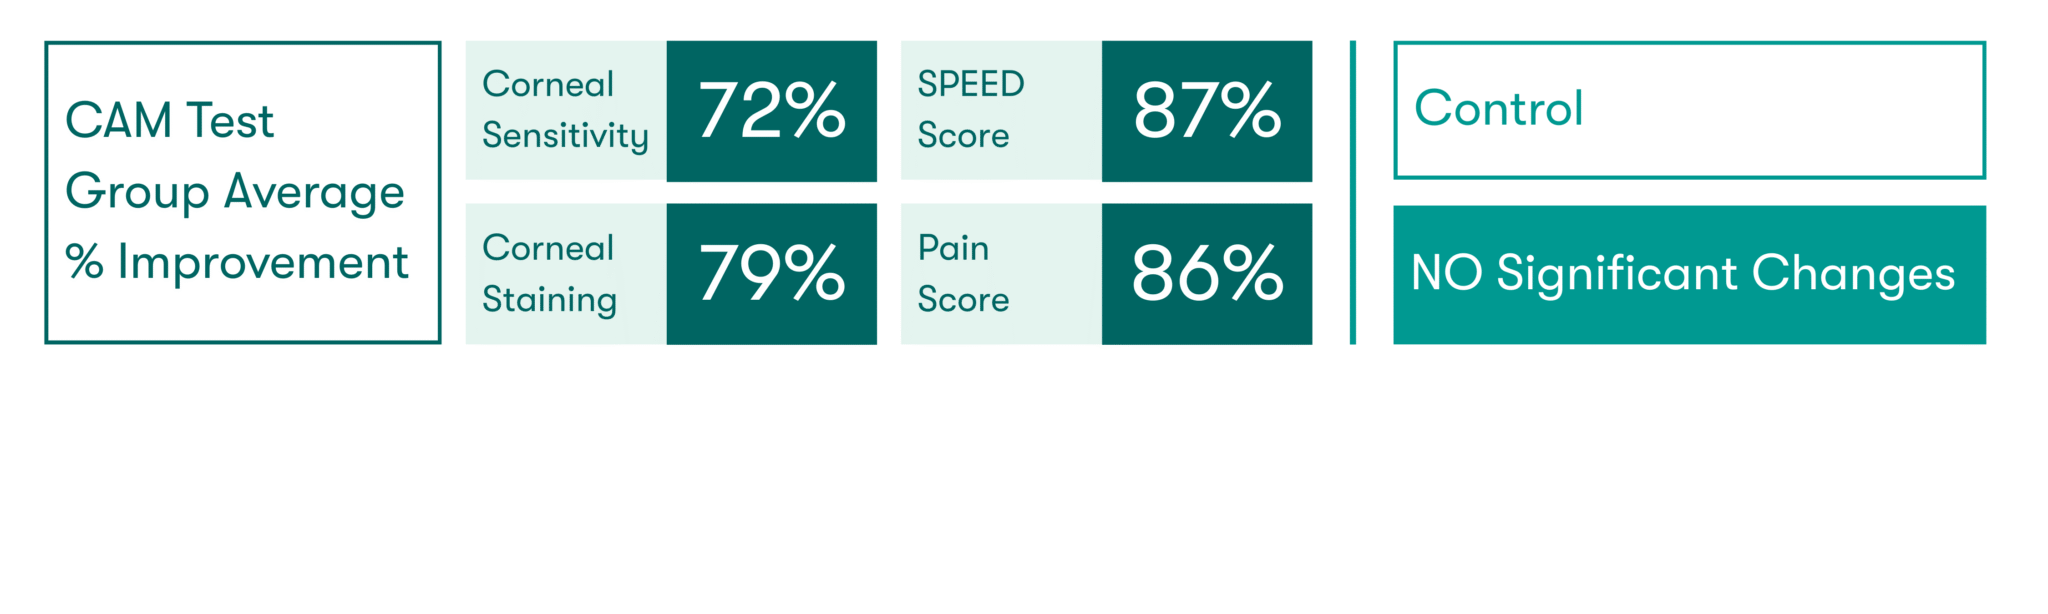

As featured in Thomas John’s clinical study, there was a significant increase in corneal sensitivity from 1 to 3 months. This improvement was significantly correlated with the increase of corneal nerve density.7

CAM preserves innate complexes found in amniotic membrane tissue that help support the regeneration of corneal surface.8,9 In a clinical study, CAM is shown to reduce signs and symptoms in ocular surface disease and restore corneal nerve density, helping improve corneal sensitivity in patients with Dry Eye Disease. 7